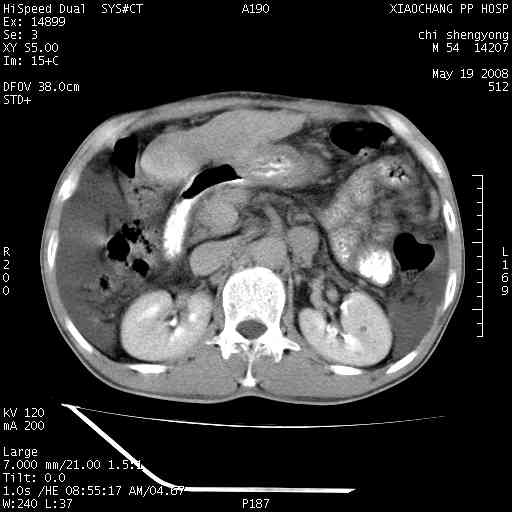

以下是引用zjzjr在2008-5-21 10:52:00的发言:[br]肝左叶巨块型肝癌伴门静脉左支瘤栓形成.肝硬化、腹水,胃底静脉曲张,脾术后改变。

以下是引用随光逐影在2008-5-21 16:20:00的发言:[br]1)肝左叶肝癌伴门静脉左支瘤栓形成,腹膜后淋巴结转移。2)肝硬化、腹水、胃底静脉曲张。3)胆囊炎。4)脾脏缺如,为切除术后所致。